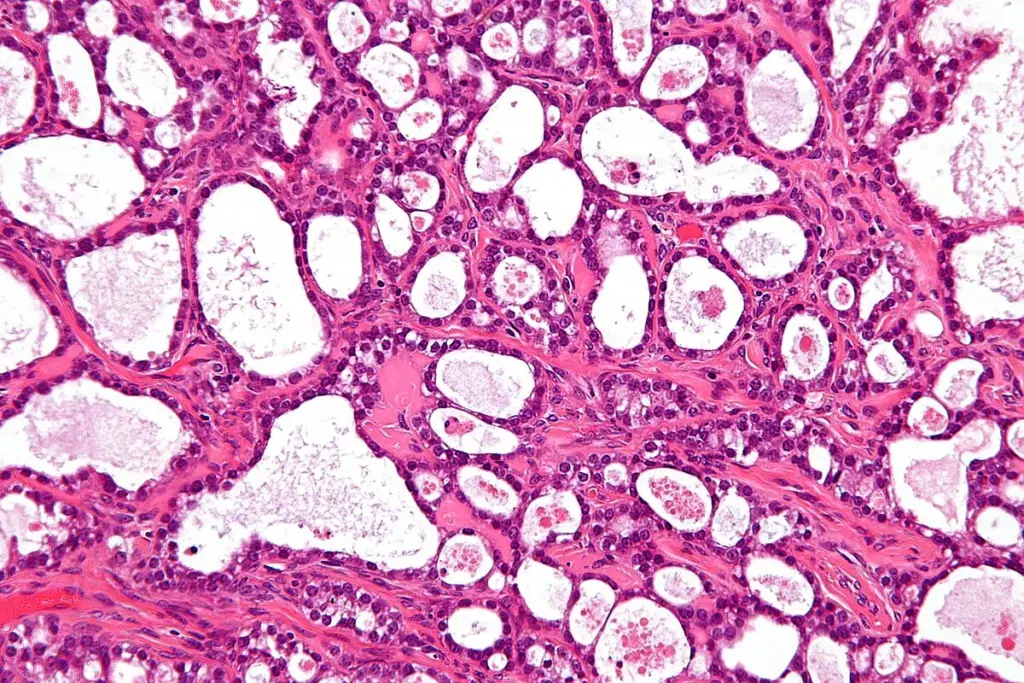

A precise cancer diagnosis is essential for creating an effective treatment plan. The process begins with a physical exam and a review of medical history. While imaging tests like CT scans, MRIs, and PET scans provide images of a tumor’s size and location, a biopsy is the definitive diagnostic tool. This involves removing a small tissue sample for a pathologist to examine. Blood tests may also be used to detect tumor markers. This collective data is then used to “stage” the cancer, a critical step that determines the extent of the disease.

The Diagnostic Process: From Symptom to Biopsy

When a symptom suggests cancer, a doctor will begin with a thorough physical exam and a review of medical history. If a specific area is suspected, the next step is typically an imaging test to visualize the inside of the body. However, cancer can only be confirmed with a biopsy. This procedure involves a specialist (such as a surgeon or radiologist) taking a sample of the suspicious tissue. A pathologist then analyzes these cells under a microscope to confirm the presence of cancer and identify its specific type.

Imaging and Laboratory Tests

Doctors use several tools to diagnose cancer and determine if it has spread:

• Imaging Tests: CT, MRI, and PET scans produce detailed images of organs and tissues to detect tumors and measure their size.

• Laboratory Tests: Blood tests, such as a complete blood count (CBC), can reveal abnormalities that may indicate cancer. Specific tests for tumor markers (substances produced by cancer cells) can also help in diagnosis and monitoring.

• Endoscopy: A procedure where a thin, lighted tube is used to look inside the body, such as a colonoscopy for colon cancer.